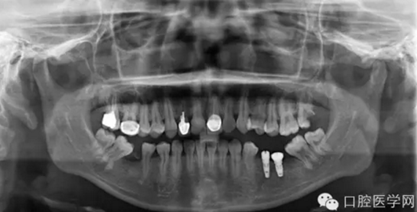

第三種是德國(guó)Ankylos種植體